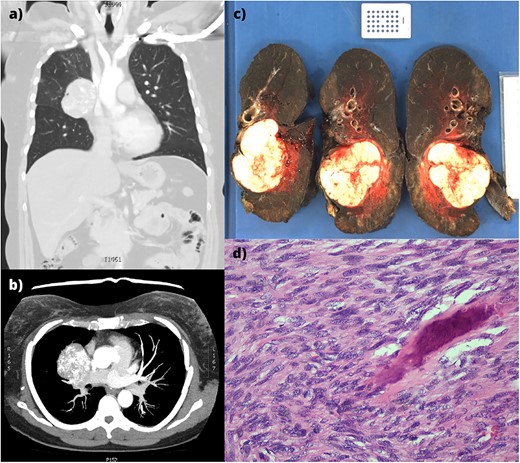

(a,b) CT imaging showing a large right hilar mass with compression of right main bronchus and superior vena cava. (c) Macroscopic appearance of the right lung containing the tumour and adjacent mediastinal structures. (d) Histopathology of the metastatic osteosarcoma, demonstrating atypical spindle cell morphology.

An en bloc intrapericardial right completion pneumonectomy and mediastinal lymph node dissection was performed via median sternotomy. Two factors favoured this approach: the hostile hilum subjected to a previous lobectomy and avoiding injury to the pedicled latissimus dorsi flap used for the initial reconstruction. The lesion was abutting but not involving the superior vena cava. Following lung deflation, the pericardium was opened and the right pulmonary artery, pulmonary vein, and azygous vein were ligated. Station 7 lymph nodes were resected, and the right main bronchus was divided. The right lung, pericardium, phrenic nerve, station 4 and 10 lymph nodes were resected en bloc (Fig. 1c). The pericardium was reconstructed with expanded polytetrafluoroethylene (0.6 mm × 10 cm × 15 cm, W. L. Gore & Associates, Inc. Flagstaff, AZ, USA). The soft tissue and sternum were closed routinely.